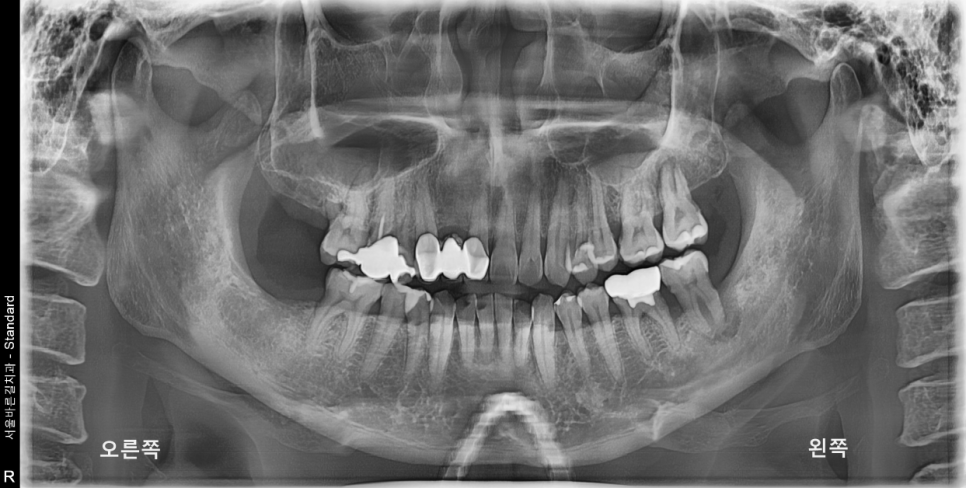

내원 당시의 사진입니다.

실제로 환자분께서는 왼쪽뿐만이 아닌

치주염으로 인해 전체적으로 골소실이 진행된 상태였습니다.